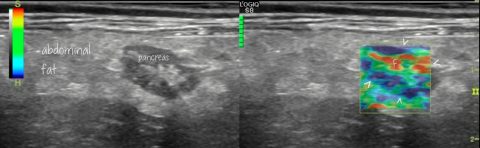

Recently I’ve seen two three-month-old dogs with multiple (numerous) small portosystemic shunts in the absence of inflammatory liver disease. The patient whose images are presented below was examined on account of acute encephalopathy with bile acids >130 umol/l and ALT > 600 (ref <100). The same in video: This flow courses via colic veins to enter … Continue reading